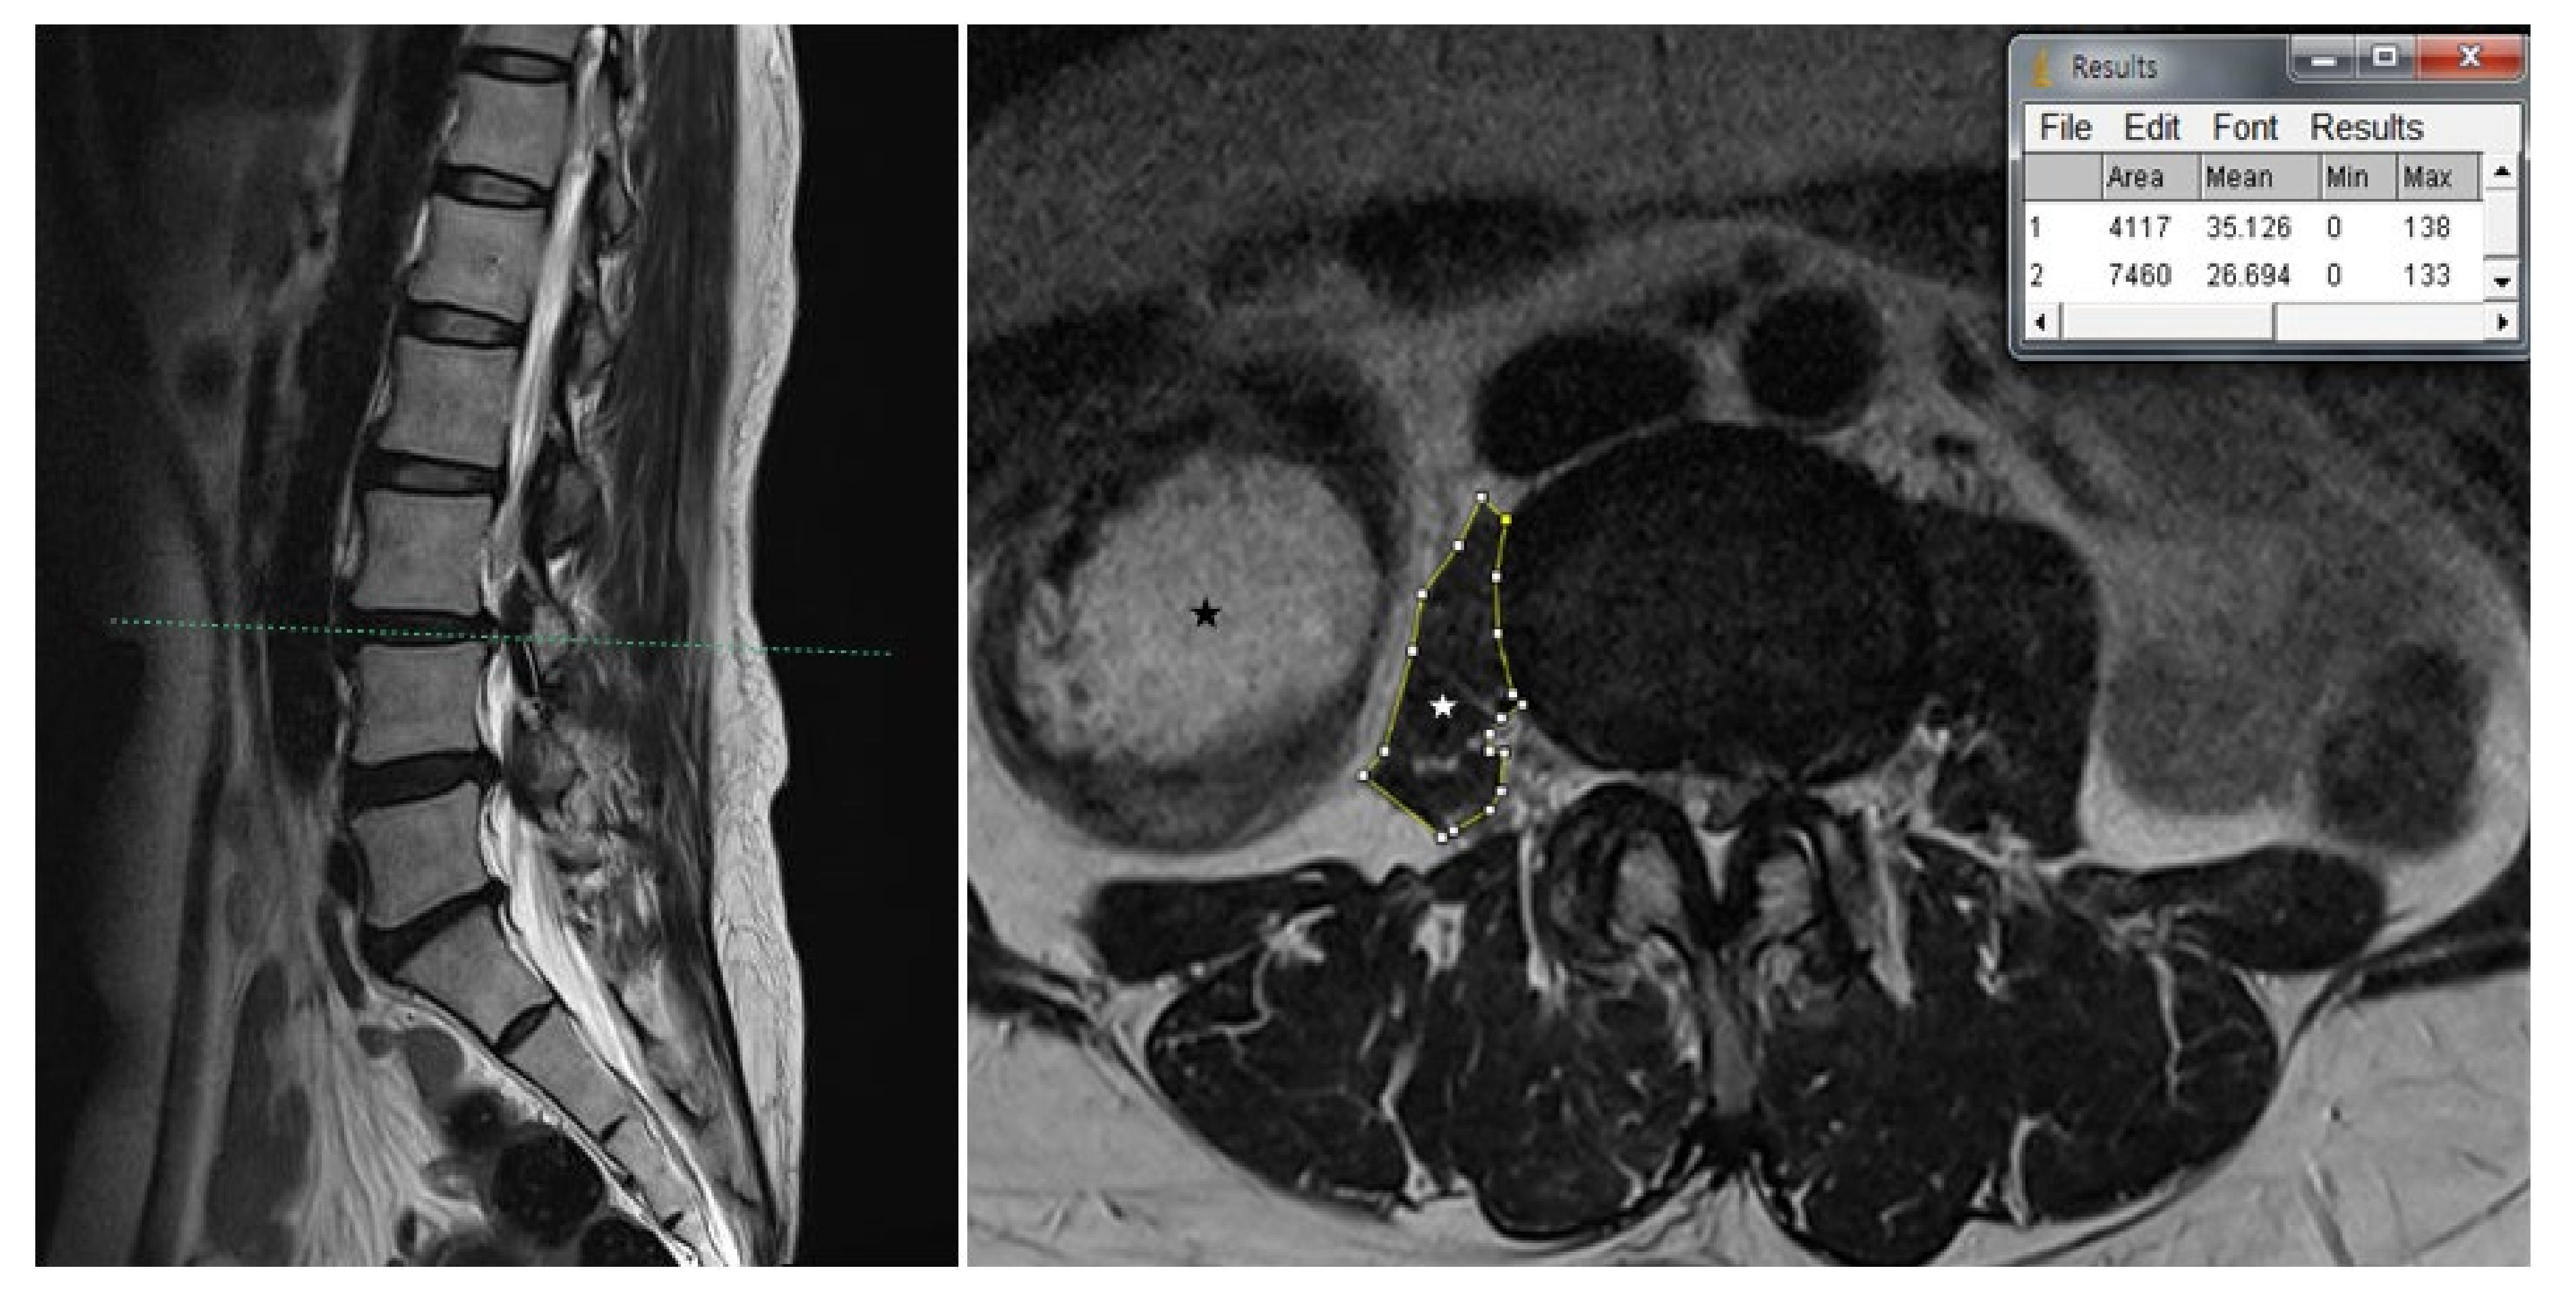

2. Case